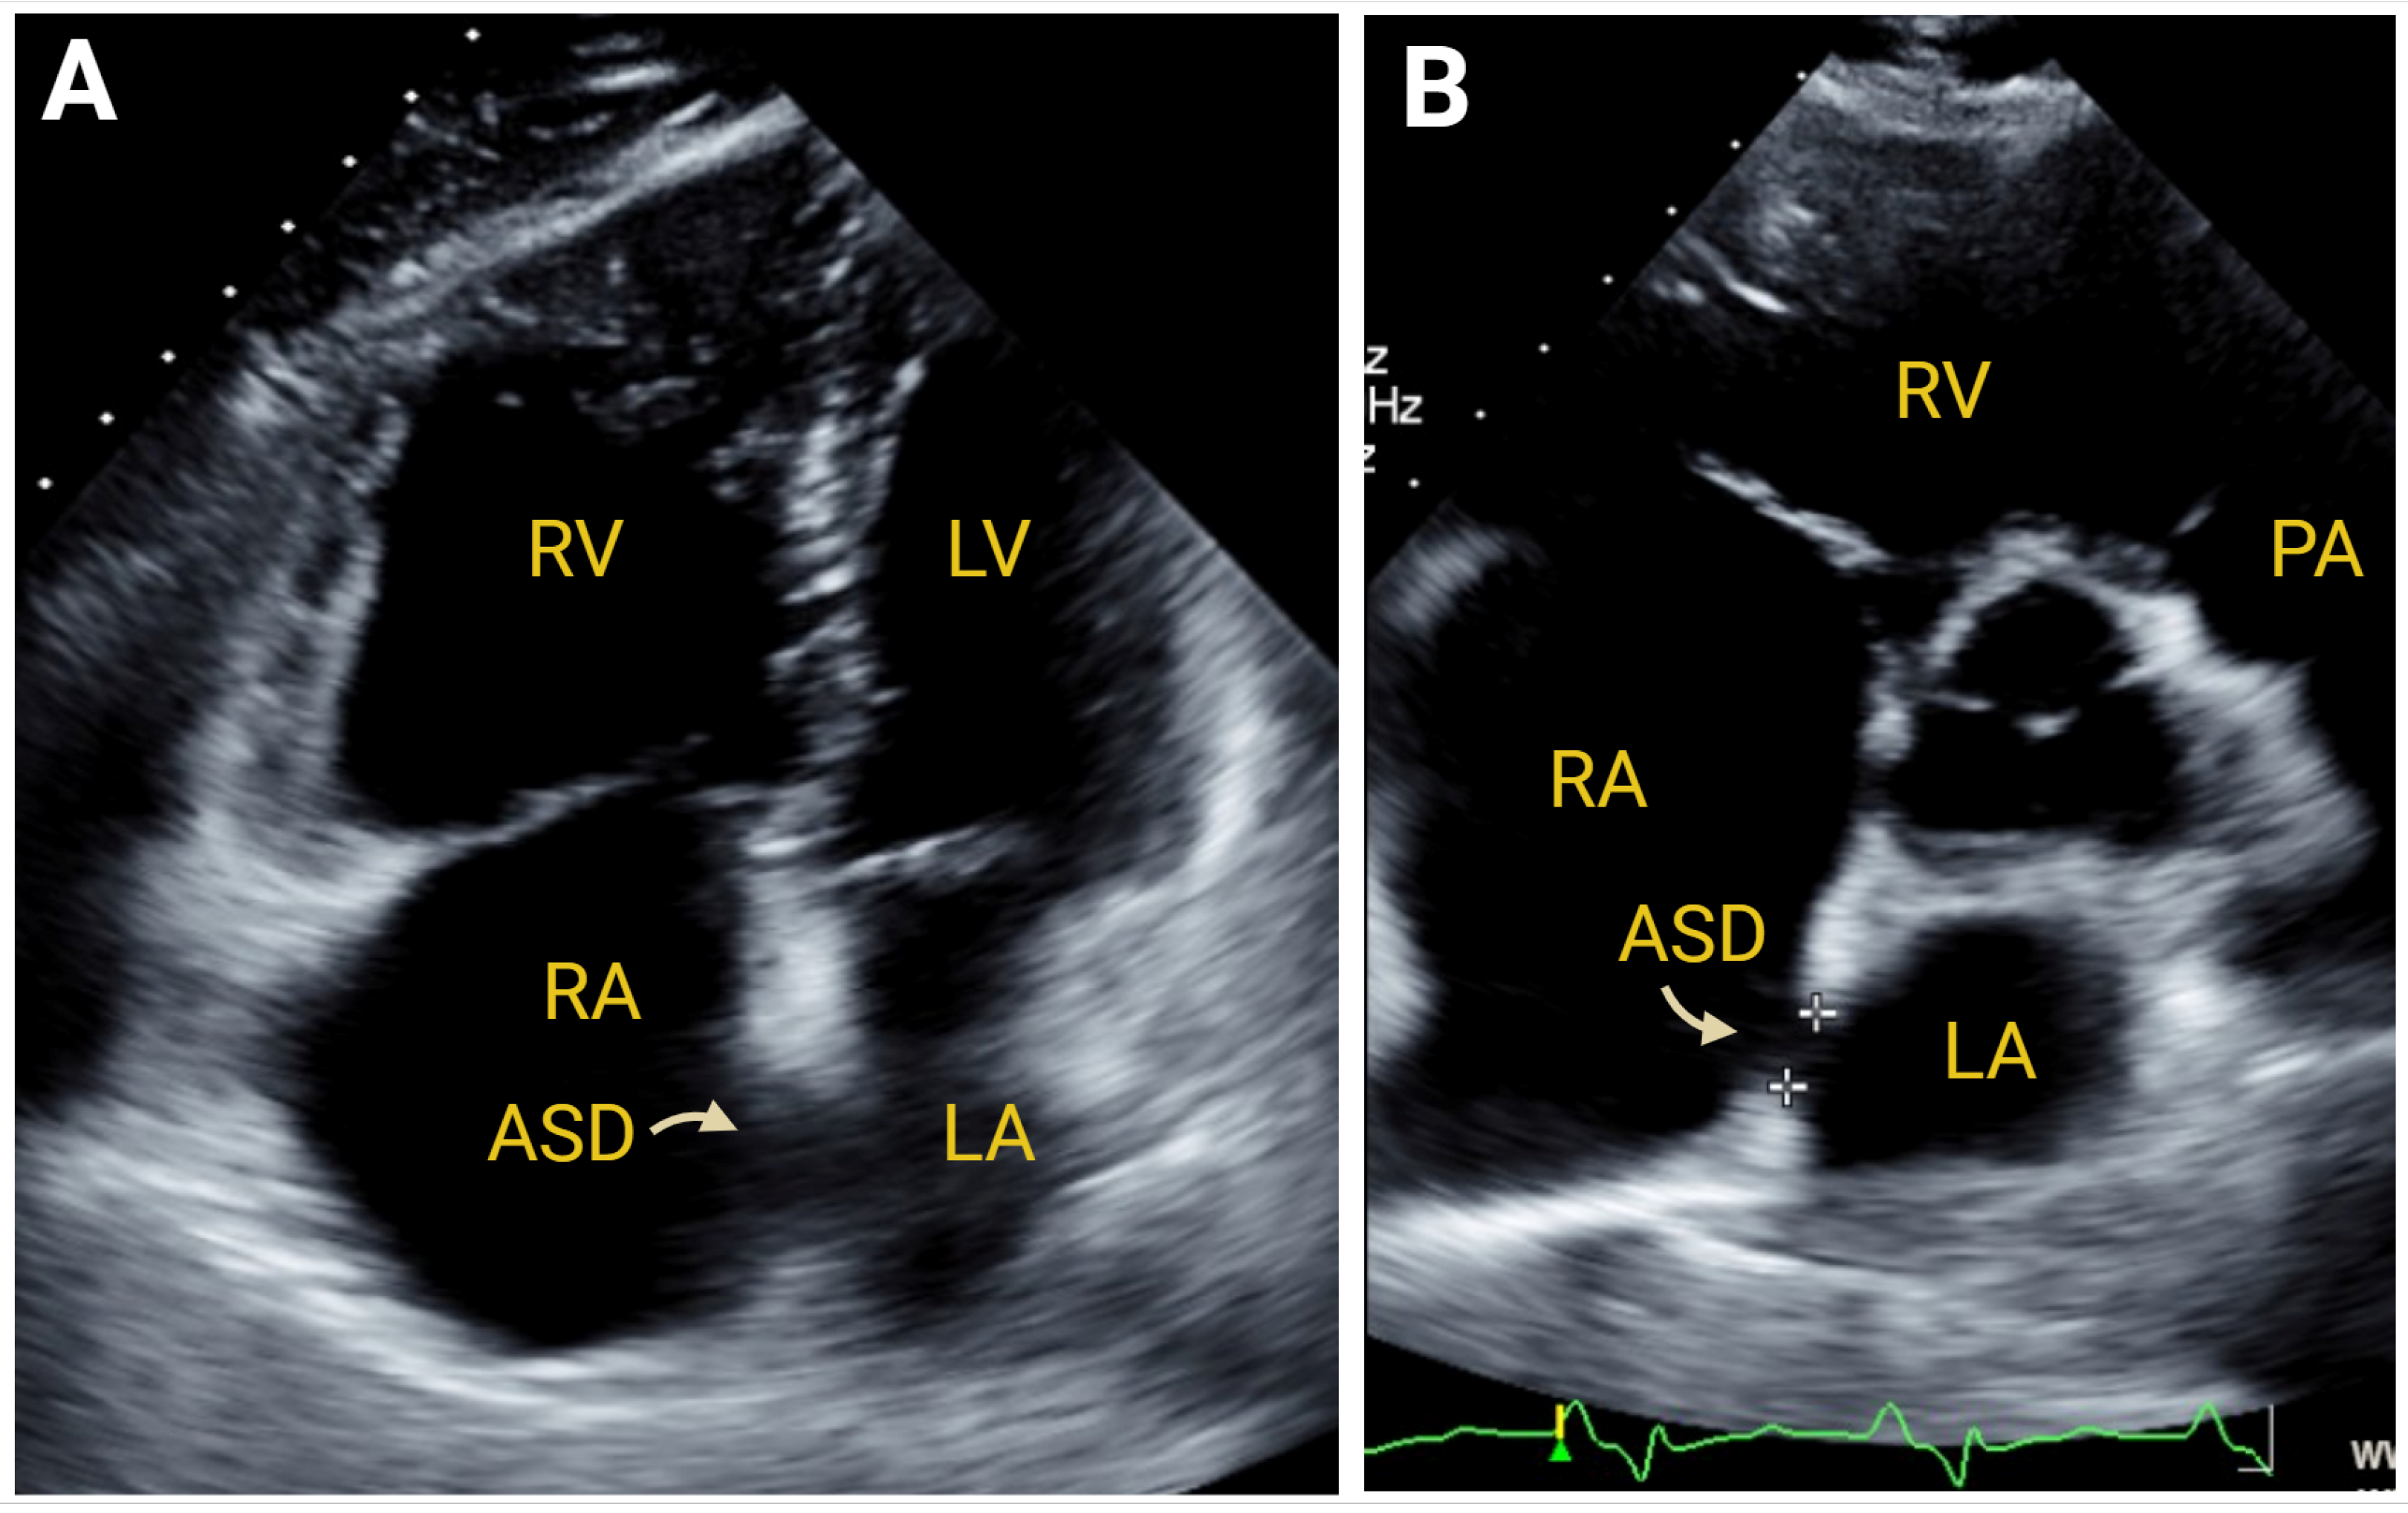

7.2.3. Simple Congenital Heart Defects

- Tikoff, G.; Schmidt, A.M.; Kuida, H.; Hecht, H.H. Heart failure in atrial septal defect. Am. J. Med. 1965, 39, 533–551. [Google Scholar] [CrossRef] [PubMed]